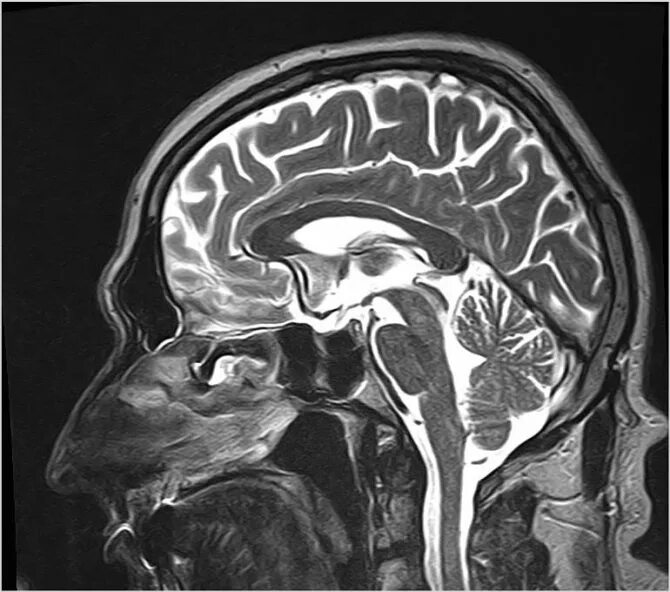

Седло в головном мозге что это